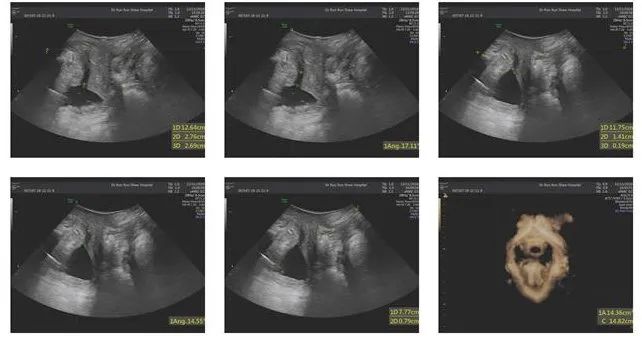

林女士的盆底彩超检查中,尿道内口的漏斗样开口,清晰可见。

康复科检查发现,林女士孕期BMI为28.3,产后4个月BMI为23.4,骨盆前倾、腹直肌分离-肚中3指,皮脂厚度31mm,1h尿垫试验12g(重度尿*禁失**),尿*禁失**生活质量问卷(IQOL)67分。

盆底肌表面肌电进一步提示,林女士快肌、慢肌及耐力均降落,盆底功能态势处于活动减弱型(松弛型)。

治疗4周后,林女士咳嗽漏尿症状明显减轻。复评结果显示BMI22.6,腹直肌分离脐中2指, 1h尿垫试验3g(中度尿*禁失**),尿*禁失**生活质量问卷(IQOL)84分,盆底快慢肌肌肉力量均有提高。